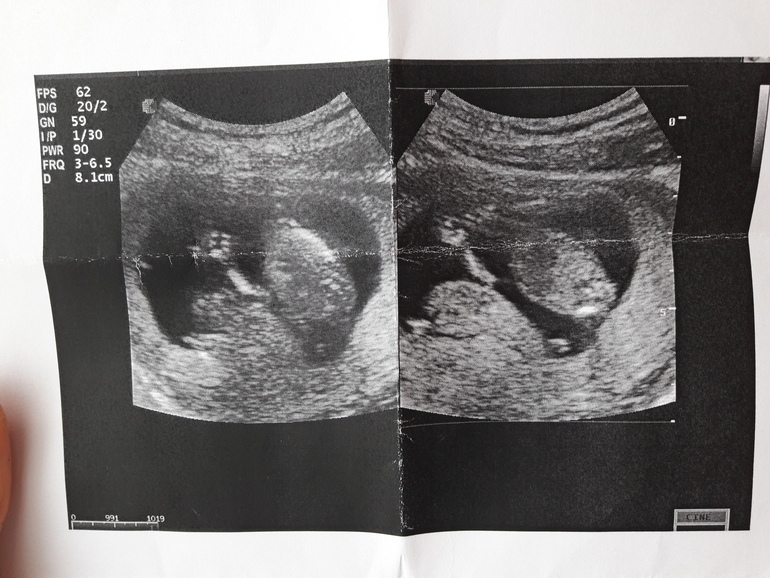

Вердикт: Гипертонус повышенный по задней стенке (+++). Краевое предлежание плаценты.Угроза прерывания беременности.

Зато я увидела вновь моё чадо, посчитали пальчики, глазки закрыты, сосет пальчики, и барахтается так- еле уловили удачные моменты для снимков))) Пол кстати не удалось глянуть, ну я думаю там 50:50

На этом снимке моя радость мне машет ручкой

А это собственно причина угрозы- не понятная шишка, с которой моё чадо катается как с горки)))) Явно в меня такой оптимист😂😂